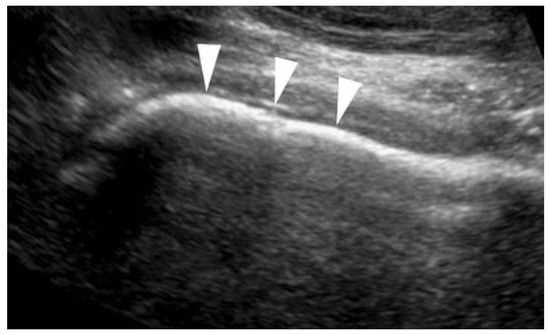

3.4.2. Cam Impingement

- Buck, F.M.; Hodler, J.; Zanetti, M.; Dora, C.; Pfirrmann, C.W.A. Ultrasound for the evaluation of femoroacetabular impingement of the cam type. Diagnostic performance of qualitative criteria and alpha angle measurements. Eur. Radiol. 2011, 21, 167–175. [Google Scholar]

- Lerch, S.; Kasperczyk, A.; Warnecke, J.; Berndt, T.; Rühmann, O. Evaluation of Cam-type femoroacetabular impingement by ultrasound. Int. Orthop. 2013, 37, 783–788. [Google Scholar] [CrossRef]

- Hsu, Y.-C.; Wu, Y.-C.; Wang, H.-H.; Lee, M.-S.; Huang, G.-S. Assessment of cam-type femoroacetabular impingement by ultrasonography: Value of anterior femoral distance measurements. Ultraschall Med. 2012, 33, E158–E165. [Google Scholar] [CrossRef]